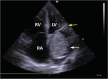

Giant left myxoma with mitral valve obstruction

We present a case of a patient admitted with acute pulmonary edema. An echocardiogram showed a giant myxoma of the left atrium causing mitral valve obstruction. The patient underwent urgent cardiac surgery for tumor resection. There were no postoperative complications, and the follow-up was uneventful.